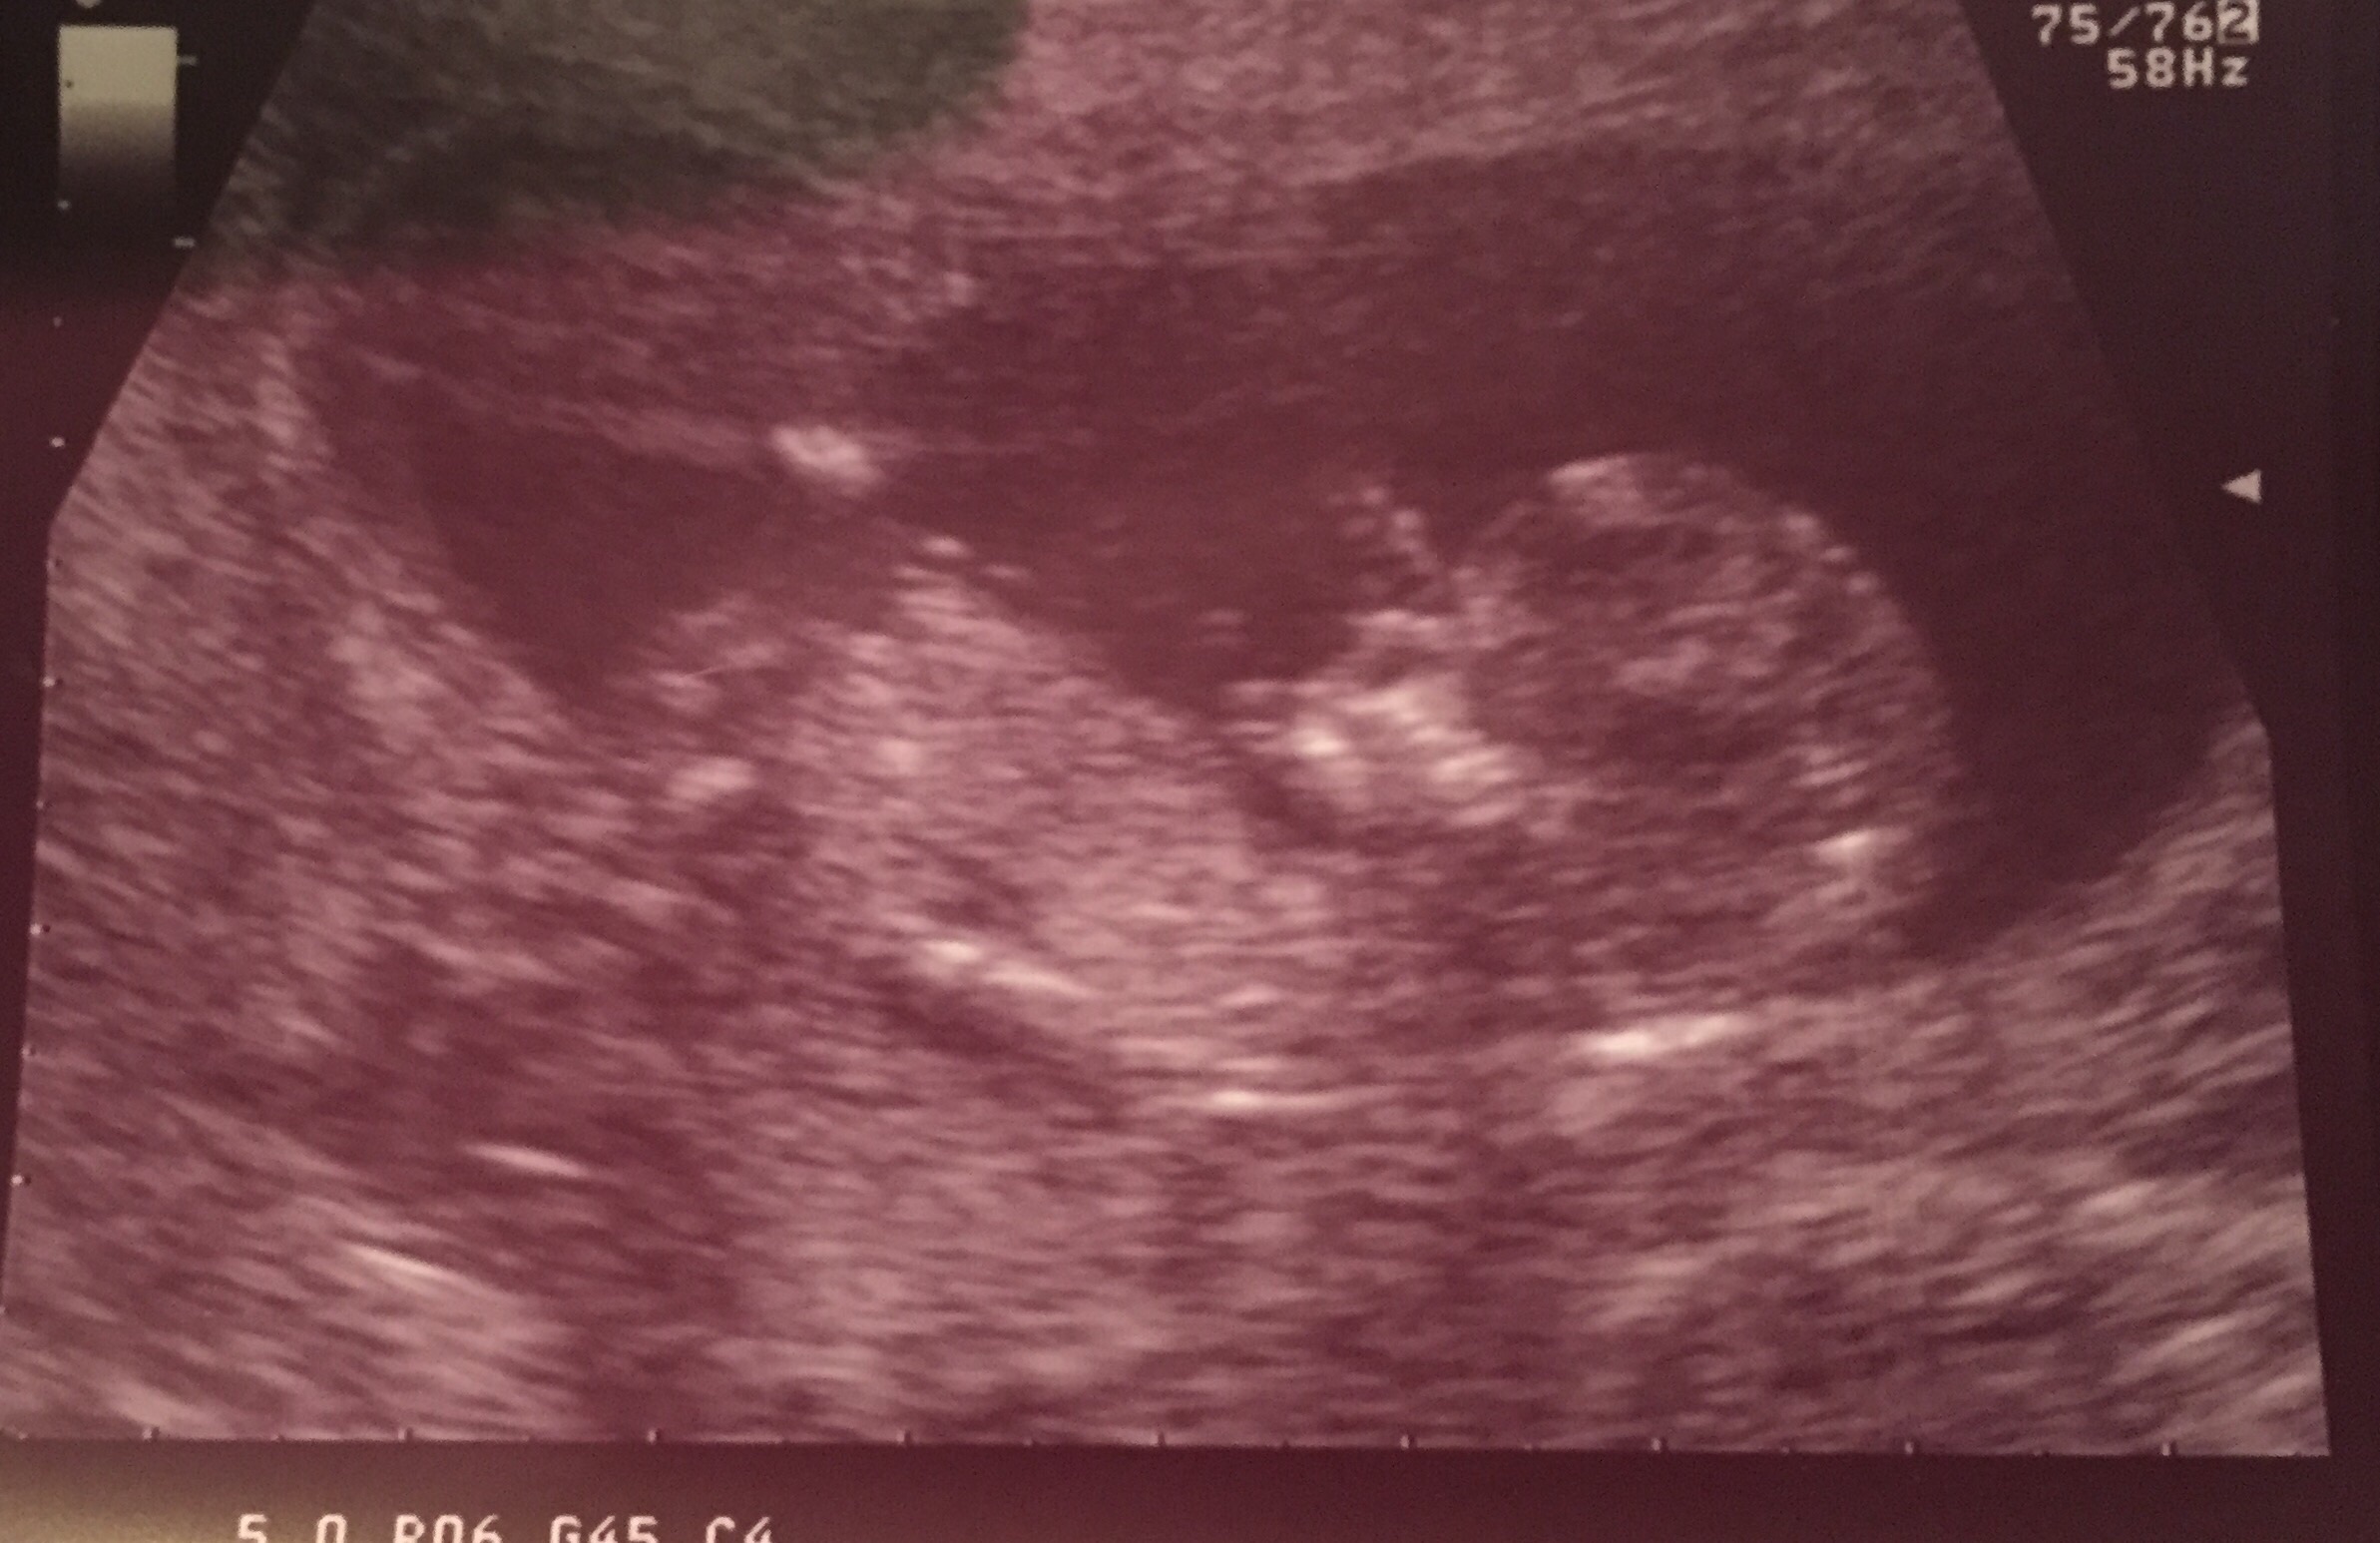

12 week ultrasound!

Yesterday was such an exciting day. My boyfriend and I went to the the 12 week ultrasound and got to see our little one. 5.9 centimeters, and 162bpm. Doctor also teased us with a 60% chance of being a girl! Baby would move when my belly was tapped. Just mind blowing.